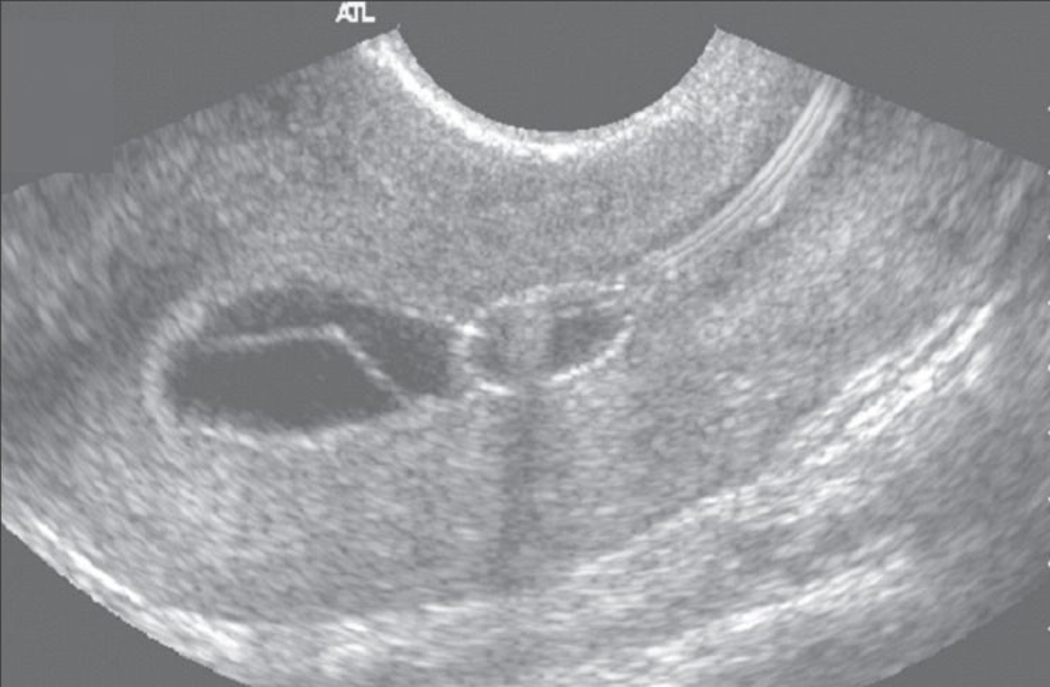

Bicornate Uterus

*